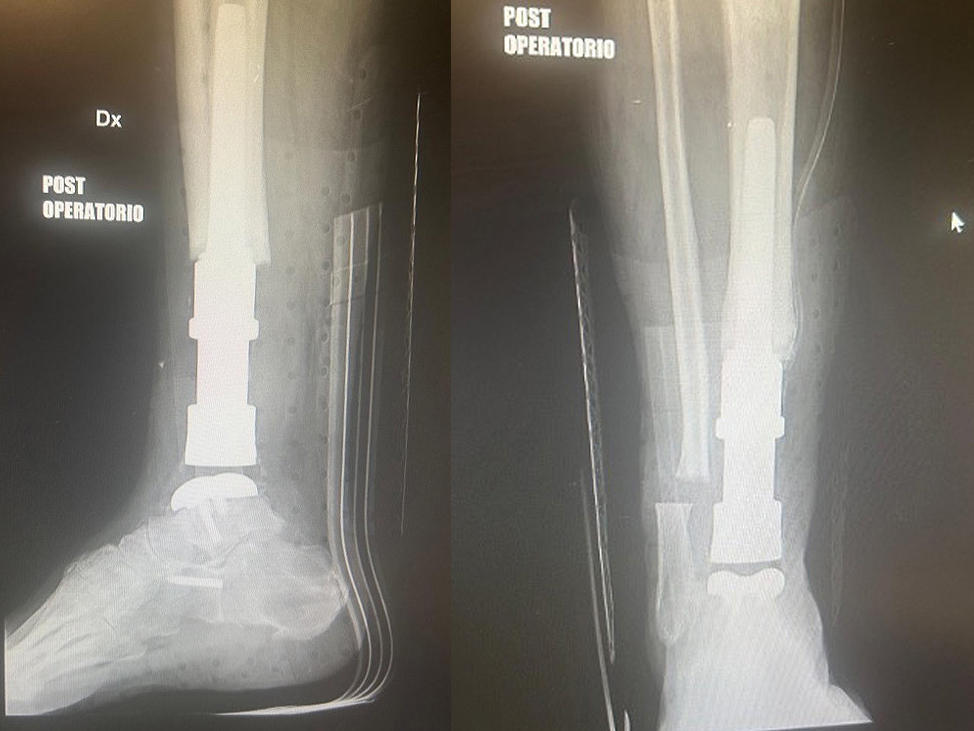

Figure 4: (Left) Postoperative X-ray (lateral view) confirming the correct positioning and cementless fixation of the custom implant. (Right) Anteroposterior view demonstrating stable alignment and restoration of articulation.

The procedure was performed using patient-specific saw guides to facilitate reproducible bone cuts and optimal implant positioning.

After resection of the failed allograft and preparation of the host bone, the custom implant was inserted. The cementless stem achieved

immediate primary stability, and the TrabecuLink® surfaces were expected to provide accelerated osseointegration. The talus component

restored articulation with the tibial replacement, allowing preserved ankle motion. Intraoperative stability was excellent, and no technical

complications occurred. Postoperatively, the patient was mobilized with partial weight-bearing and transitioned into a structured rehabilitation

program. Early X-rays confirmed correct alignment and stable fixation.